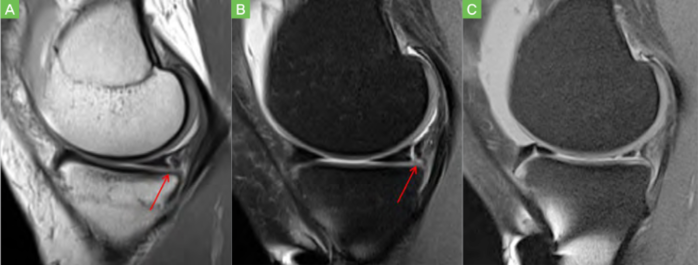

| ▲램프병변 |

Ramp는 층을 잇는 경사진 마루나 길이란 의미로, 내측반월연골판 후각의 변연부 파열이 무릎 앞쪽에서는 잘 보이지 않는 특별한 부위를 말한다. 램프병변은 전방십자인대 파열손상 후 종아리뼈가 원위치로 돌아오는 과정에서 발생한다. 유병률은 16.5~29.7%로 다양하게 보고 있는데, 이는 연구마다 진단 방법에 차이가 있기 때문이다. 램프병변은 MRI로도 진단율이 상대적으로 낮고, 관절경으로 보아도 전방에서는 잘 보이지 않아 진단이 의심되면 후방구획을 관찰해야 진단율을 높일 수 있다.